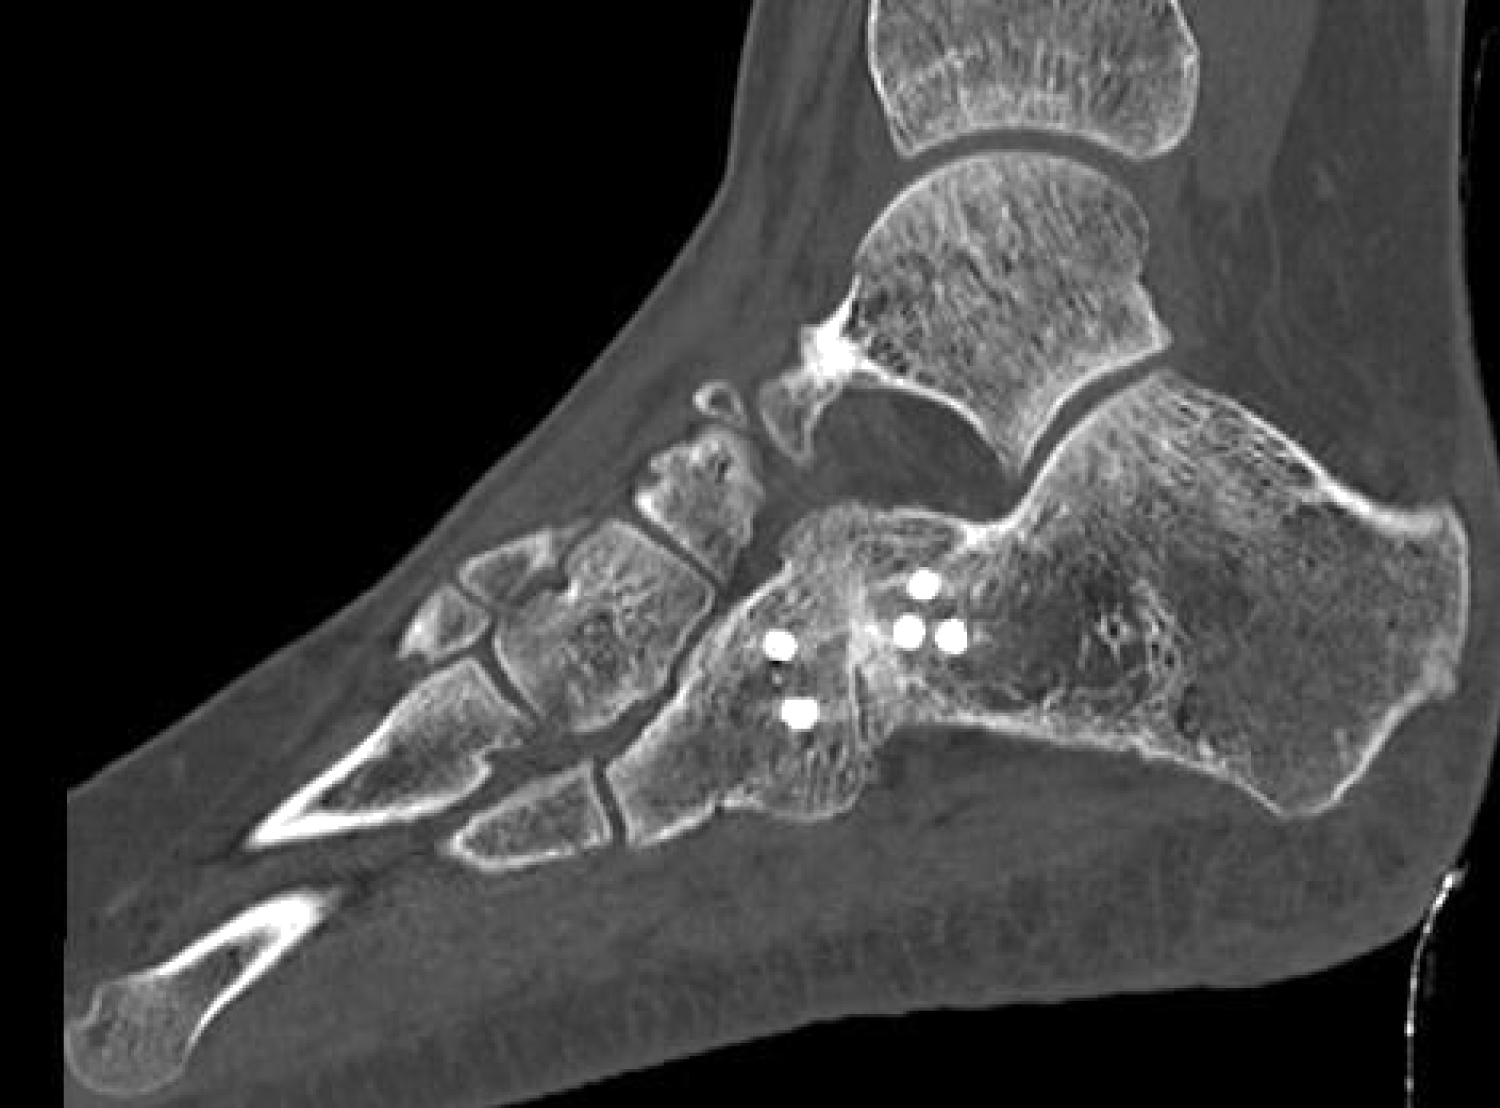

Two years after the initial trauma, early 2017, she presented at our clinic for a second opinion. She stopped working due to persisting ankle pain during weight-bearing. Clinical examination showed anterior-posterior instability and pain located over the CC-joint. A SPECT-CT was taken, showing a hotspot over the CC-joint and a residual avulsion of the dorsolateral calcaneal fragment (Figure 3). The CC-joint also had a degenerative aspect.

Figure 3: Sagittal view on SPECT-CT taken in January 2017, showing a non-union of the avulsion fracture and arthritis of the calcaneo-cuboid joint. View Figure 3